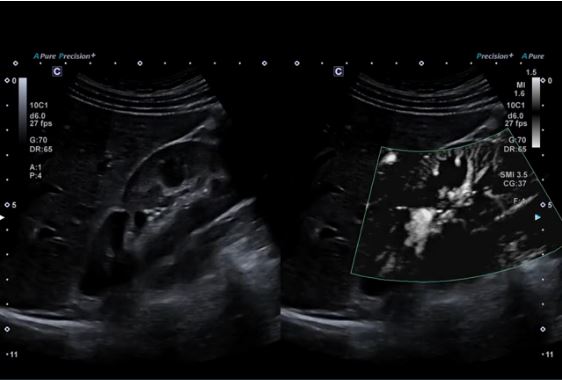

Технологія візуалізації мікропотоків (SMI) відображає кровотоки низької швидкості у нирці.

Висока частота кадрів підтримується за допомогою SMI відображаючи перфузію в нирці при використанні мікроконвексного датчика.

Конвексний датчик PVU-574BT (10C1)

Високочастотний монокристалічний конвексний датчик забезпечує високу просторову роздільну здатність і проникнення для підвищення клінічної впевненості в акушерських, неонатальних  та інших дослідженнях.